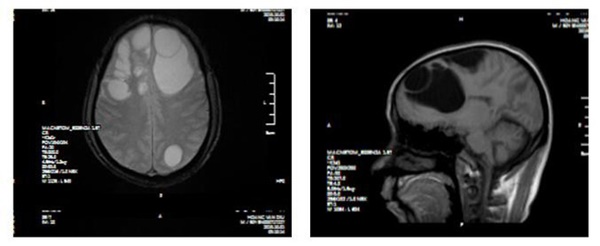

Tại Bệnh viện đa khoa tỉnh Phú Thọ, bệnh nhân được chỉ định chụp CT sọ não, kết quả cho thấy ổ sán não khổng lồ ở cả hai bán cầu trái và phù não diện rộng. Bệnh nhân được chỉ định can thiệp ngoại khoa.

Phim chụp cho bệnh nhân

Ổ sán đươc phát hiện trong não bệnh nhân